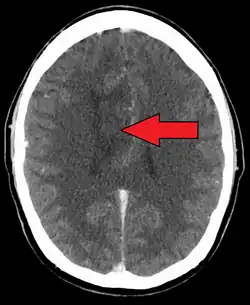

Oligoastrocytom je název pro širokou škálu variant nádorů gliových buněk, astrocytomů a oligodendrogliomů.[1] Průměrný věk pacientů je 42 let.